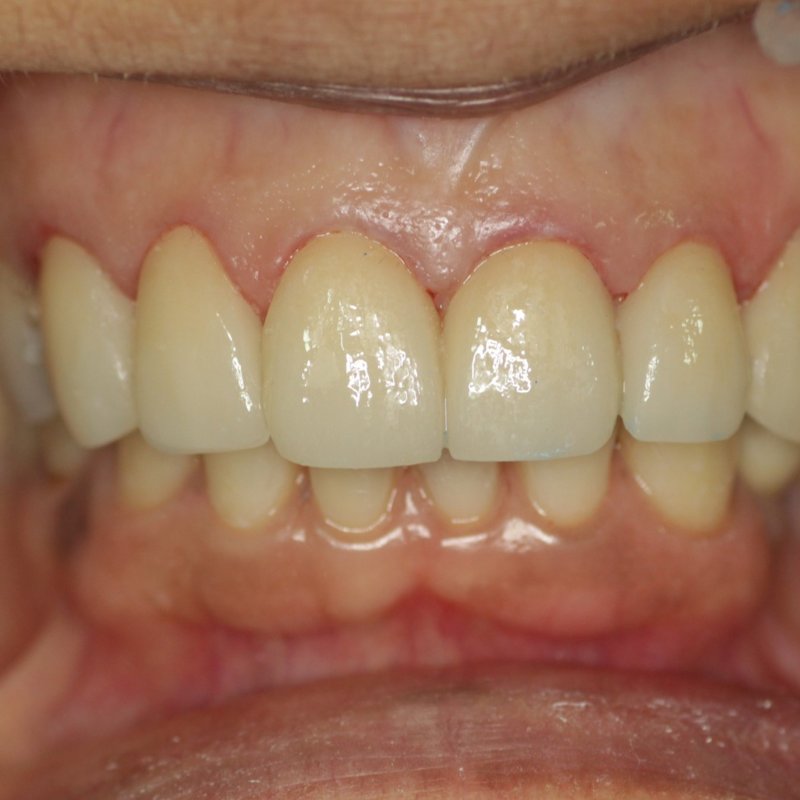

Full Arch Prosthetics

Edentulous to full smile

A full-arch restoration giving back form, function, and confidence — engineered for long-term wear and natural aesthetics.